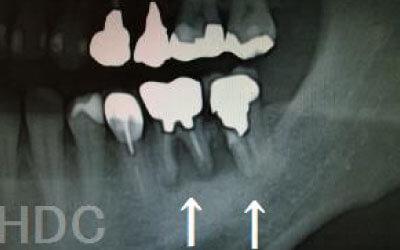

しばらくすると抜けたままでも慣れてきますが、大きな問題が発生します。

1 周囲の歯が早く抜ける

抜けた歯にかかるはずだった噛む力が、無意識のうちに他の歯に負担をかけてしまいます。その結果、残っている歯が急に折れてしまい、最終的に抜歯が必要になることがよくあります。

2 歯が傾いてくる、落ちてくる

歯はお互いに支え合ってバランスを取っています。ですので、歯が抜けるとその支えがなくなり、抜けた部分の隣の歯が倒れたり、上の歯が下に下がってくることがあります。